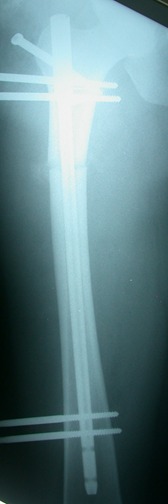

التثبيت الخارجي بتقنية

قد يتم احتياج تركيب مثبت خارجي لاصلاح تشوهات او معالجة عظم او تسوس عظمي بكلا عظمتي الساق والفخذ وبالامكان الاستخدام ايضا في علاج تيبسات المفاصل والعيوب الخلقية وخشونة مفصل الكاحل

تتوفر تقنية مثبت خارجي (TSF) لعلاج التشوه عن طريق الكمبيوتر وبدقة فائقة لعلاج فرق الطول والتشوه وعيب الدوران وتعويض العظام المفقودة في عظم الساق , كما يتم استخدام المثبت الجانبي اورثوفكس لعلاج الامراض السابقة الذكر بعظم الفخد